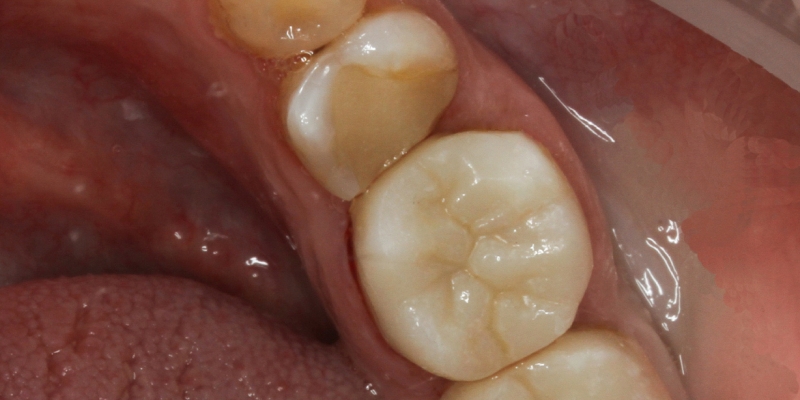

До и после лечения

Керамическая накладка Overlay полностью перекрывает щёчную и нёбную поверхности зуба. Конструкция обеспечивает идеальное смыкание с тканями ротовой полости, повторяет индивидуальные особенности рельефа естественных зубов. Накладка практически не даёт усадку, препятствуя повторному образованию кариеса. Материал накладки не темнеет и не окисляется.